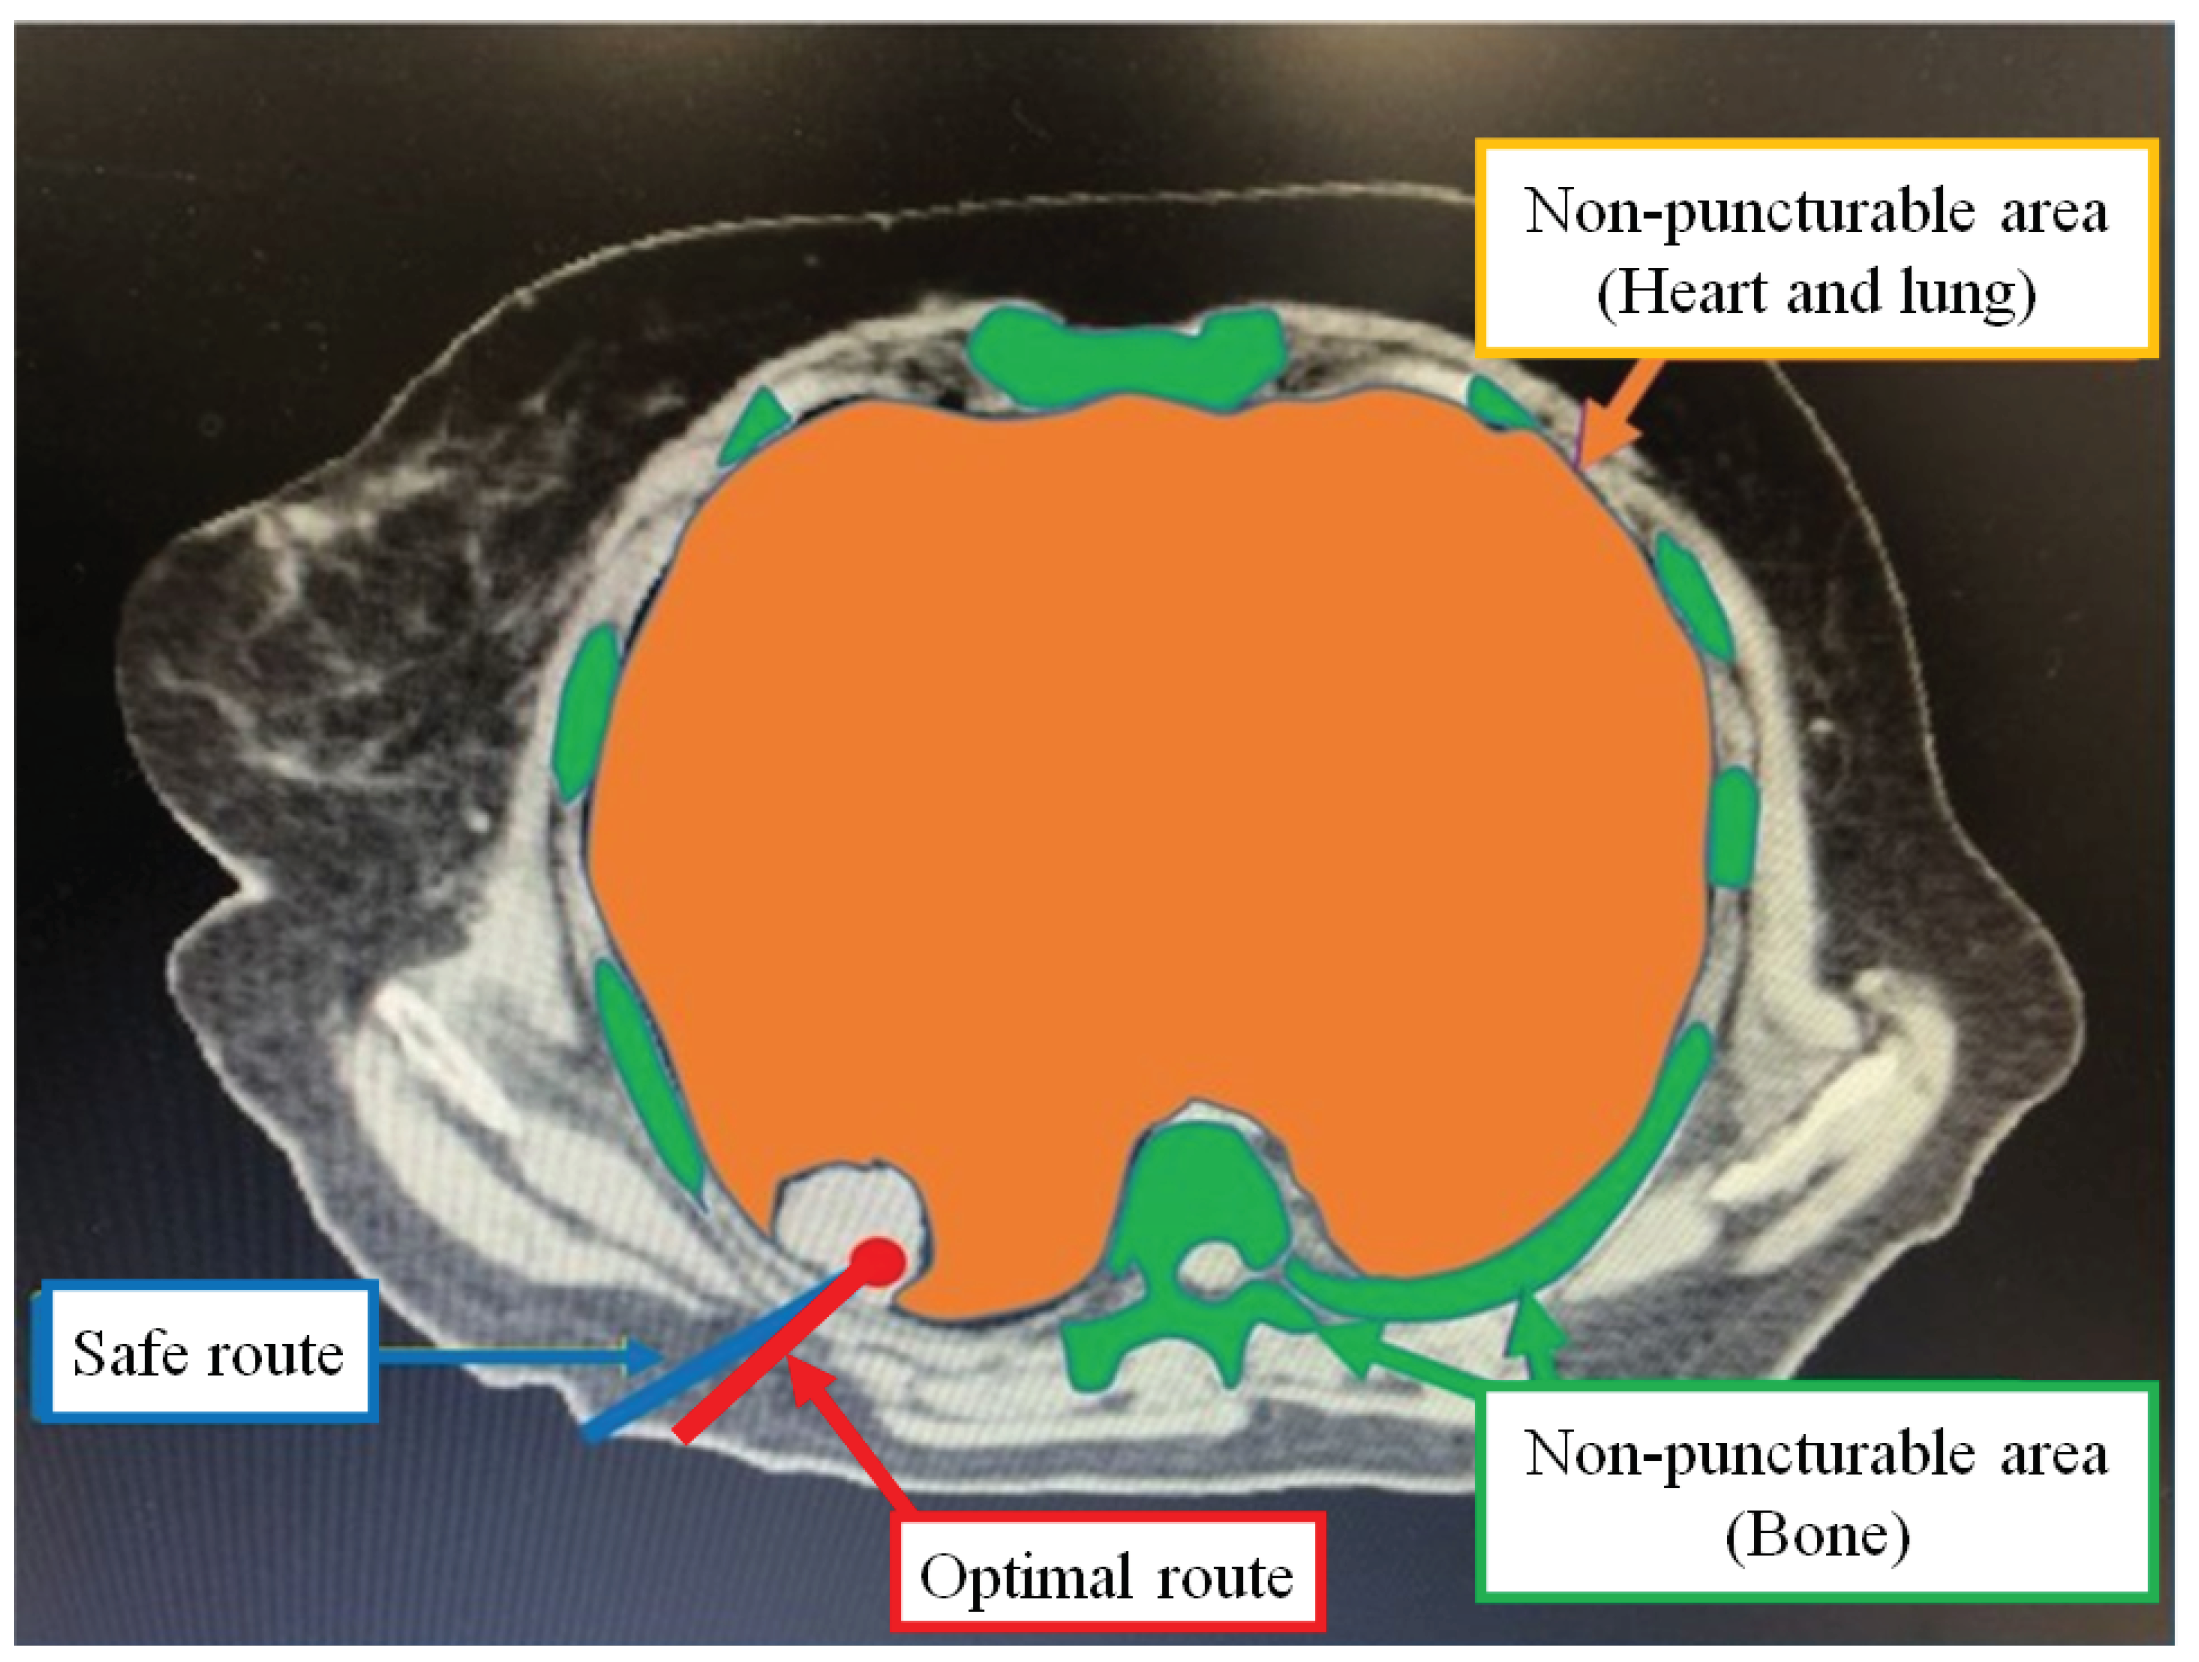

3.2.2. Safe Route

An example of a safe route for a CT image puncture is shown in Figure 3. The safe route has the longest distance away from a pixel on the puncture route to a pixel in the non-puncturable area. During the actual puncture, there is some deviation between the predefined puncture route and the trajectory of the puncture needle. The safe route naturally increases the puncture distance compared to the shortest route. On the other hand, since the possibility of puncturing a non-puncturable area is reduced, the physician can make the puncture more safely.

3.2.3. Optimal Route

In Figure 3, we show an example of the optimal route for a CT image puncture. The optimal route is a route suitable for puncture according to many physicians based on the shortest route and the safe route. By selecting the optimal route, the physician can perform the puncture while giving consideration to both shortening the puncture distance and preventing medical accidents.

Figure 3. Example of a safe route and optimal route.

Jimaging 10 00251 g003